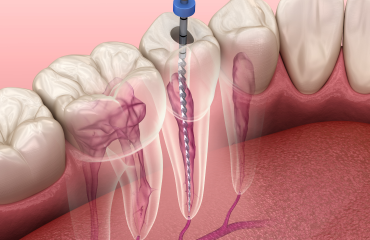

Endodontie

L’endodontie, ou traitement de canal, traite les infections des racines dentaires pour préserver les dents naturelles. Grâce à des techniques éprouvées, nous soulageons la douleur et restaurons la santé dentaire, évitant ainsi l’extraction.